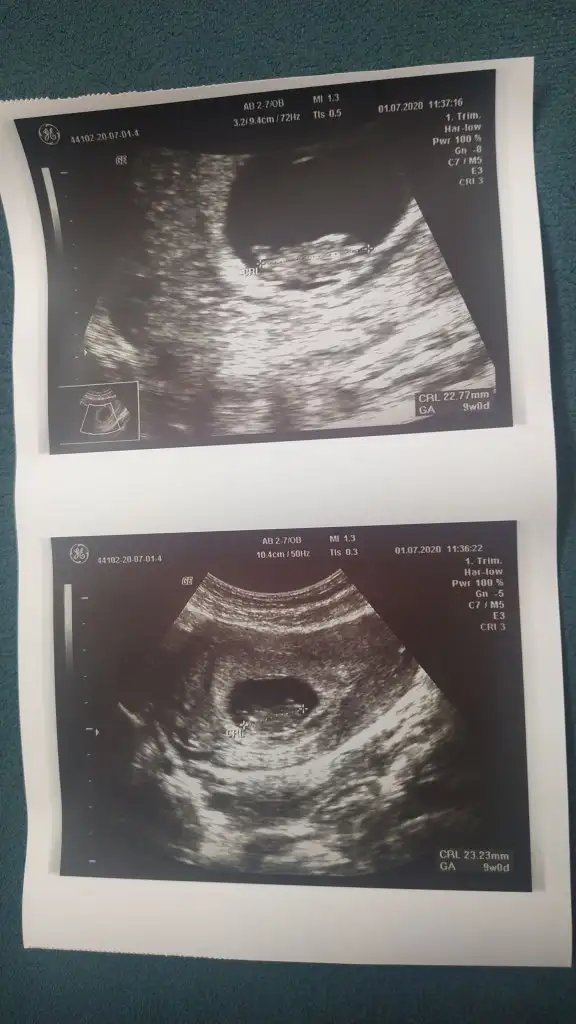

13+5 de nub biter ama kıza benzettim yani sagdakiniKizlar size iki tane resim biri kizima biri ogluma ait sizce hangisi kiz hangisi erkekEki Görüntüle 2657161 Eki Görüntüle 2657162

Doktor %50 tahmin ederim dedi istemedik ağustosta tam net söylicek inşallahErkek gibi sanki

Hıım tmm cnm zaten 12-13 haftalıkken gideceğim ozamanda paylaşırım :) yorumladığın için saol :)En iyi 11 12 13 şimdilik erkek kese konumu